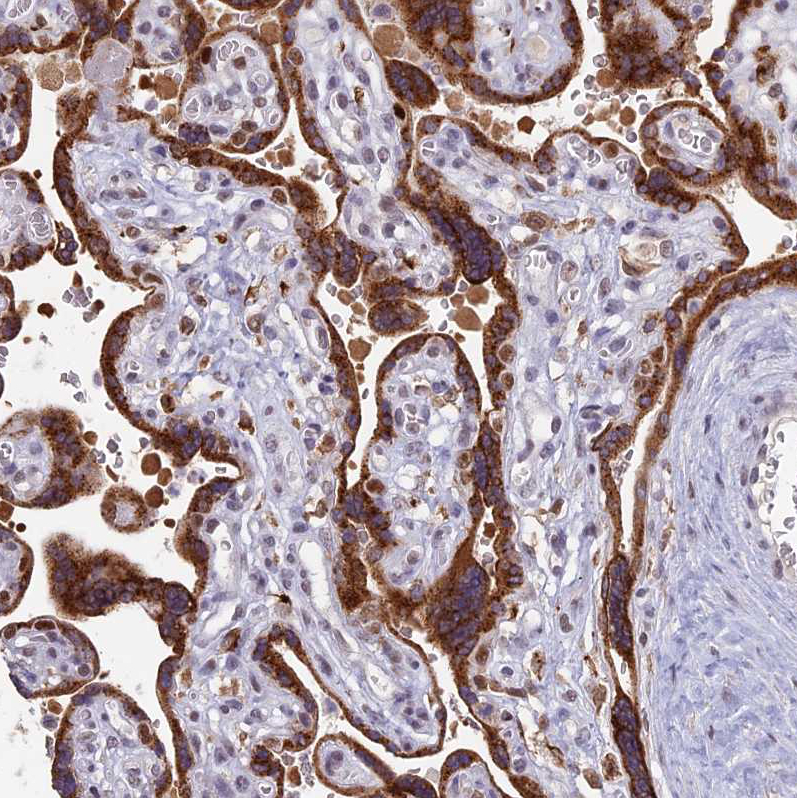

Immunohistochemical staining of human heart muscle shows moderate to strong granular cytoplasmic positivity in cardiomyocytes.